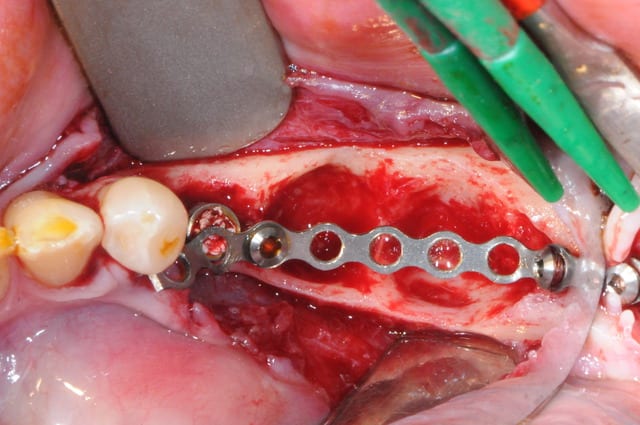

4-5-6-7 sciage de la mesh titane et positionnement in situ d'un bout à l'autre de l'arcade.

enfin, mise en place d'une membrane péricarde Jason de 30*50 (je crois)

3- j'ai profité de la stabilité de la mesh comme piquet de tente pour bourrer la cavité avec du MAXGRAFT (os humain)..

4-5- un peu de A-PRF (the king !)

6- le plus important des sutures hermétiques et une gencive immobile en fin d'intervention

7 les radios post-op